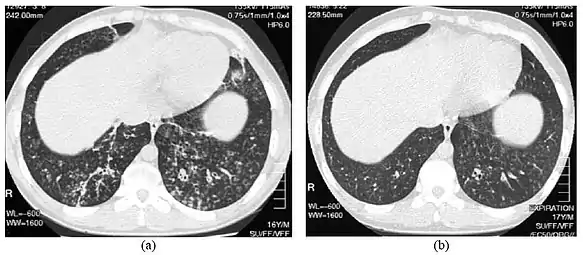

- High-resolution computed tomography scan of the thorax

- High resolution computed tomography (HRCT) images of the lower chest in a 16-year-old boy initially diagnosed with DPB (left), and 8 weeks later (right) after a 6-week course of treatment with erythromycin. The bilateral bronchiectasis and prominent centri-lobular nodules with a "tree-in-bud" pattern shows noticeable improvement.

The diagnosis of DPB requires analysis of the lungs and bronchiolar tissues, which can require a lung biopsy, or the more preferred high resolution computed tomography (HRCT) scan of the lungs.[7] The diagnostic criteria include severe inflammation in all layers of the respiratory bronchioles and lung tissue lesions that appear as nodules within the terminal and respiratory bronchioles in both lungs.[4] The nodules in DPB appear as opaque lumps when viewed on X-rays of the lung, and can cause airway obstruction, which is evaluated by a pulmonary function test, or PFT.[6] Lung X-rays can also reveal dilation of the bronchiolar passages, another sign of DPB. HRCT scans often show blockages of some bronchiolar passages with mucus, which is referred to as the "tree-in-bud" pattern.[7] Hypoxemia, another sign of breathing difficulty, is revealed by measuring the oxygen and carbon dioxide content of the blood, using a blood test called arterial blood gas. Other findings observed with DPB include the proliferation of lymphocytes (white blood cells that fight infection), neutrophils, and foamy histiocytes (tissue macrophages) in the lung lining. Bacteria such as H. influenzae and P. aeruginosa are also detectable, with the latter becoming more prominent as the disease progresses.[4][5] The white blood, bacterial and other cellular content of the blood can be measured by taking a complete blood count (CBC). Elevated levels of IgG and IgA (classes of immunoglobulins) may be seen, as well as the presence of rheumatoid factor (an indicator of autoimmunity). Hemagglutination, a clumping of red blood cells in response to the presence of antibodies in the blood, may also occur. Neutrophils, beta-defensins, leukotrienes, and chemokines can also be detected in bronchoalveolar lavage fluid injected then removed from the bronchiolar airways of individuals with DPB, for evaluation.[4][9]